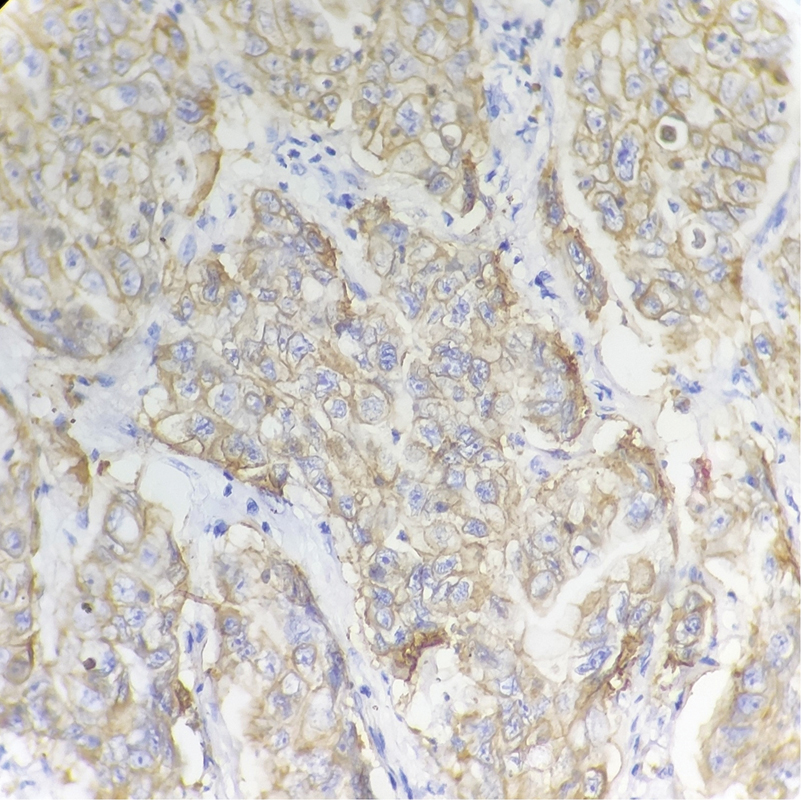

Adenocarcinoma with moderate differentiation (grade 2) displayed highest HER2/neu positivity (score 3 + ) ([Fig. 3]) followed by poor differentiation (grade 3).

Fig. 3 Moderately differentiated gastric adenocarcinoma showing positive membranous staining for HER2/neu; immunohistochemistry ×40. HER2, human epidermal growth factor receptor 2.